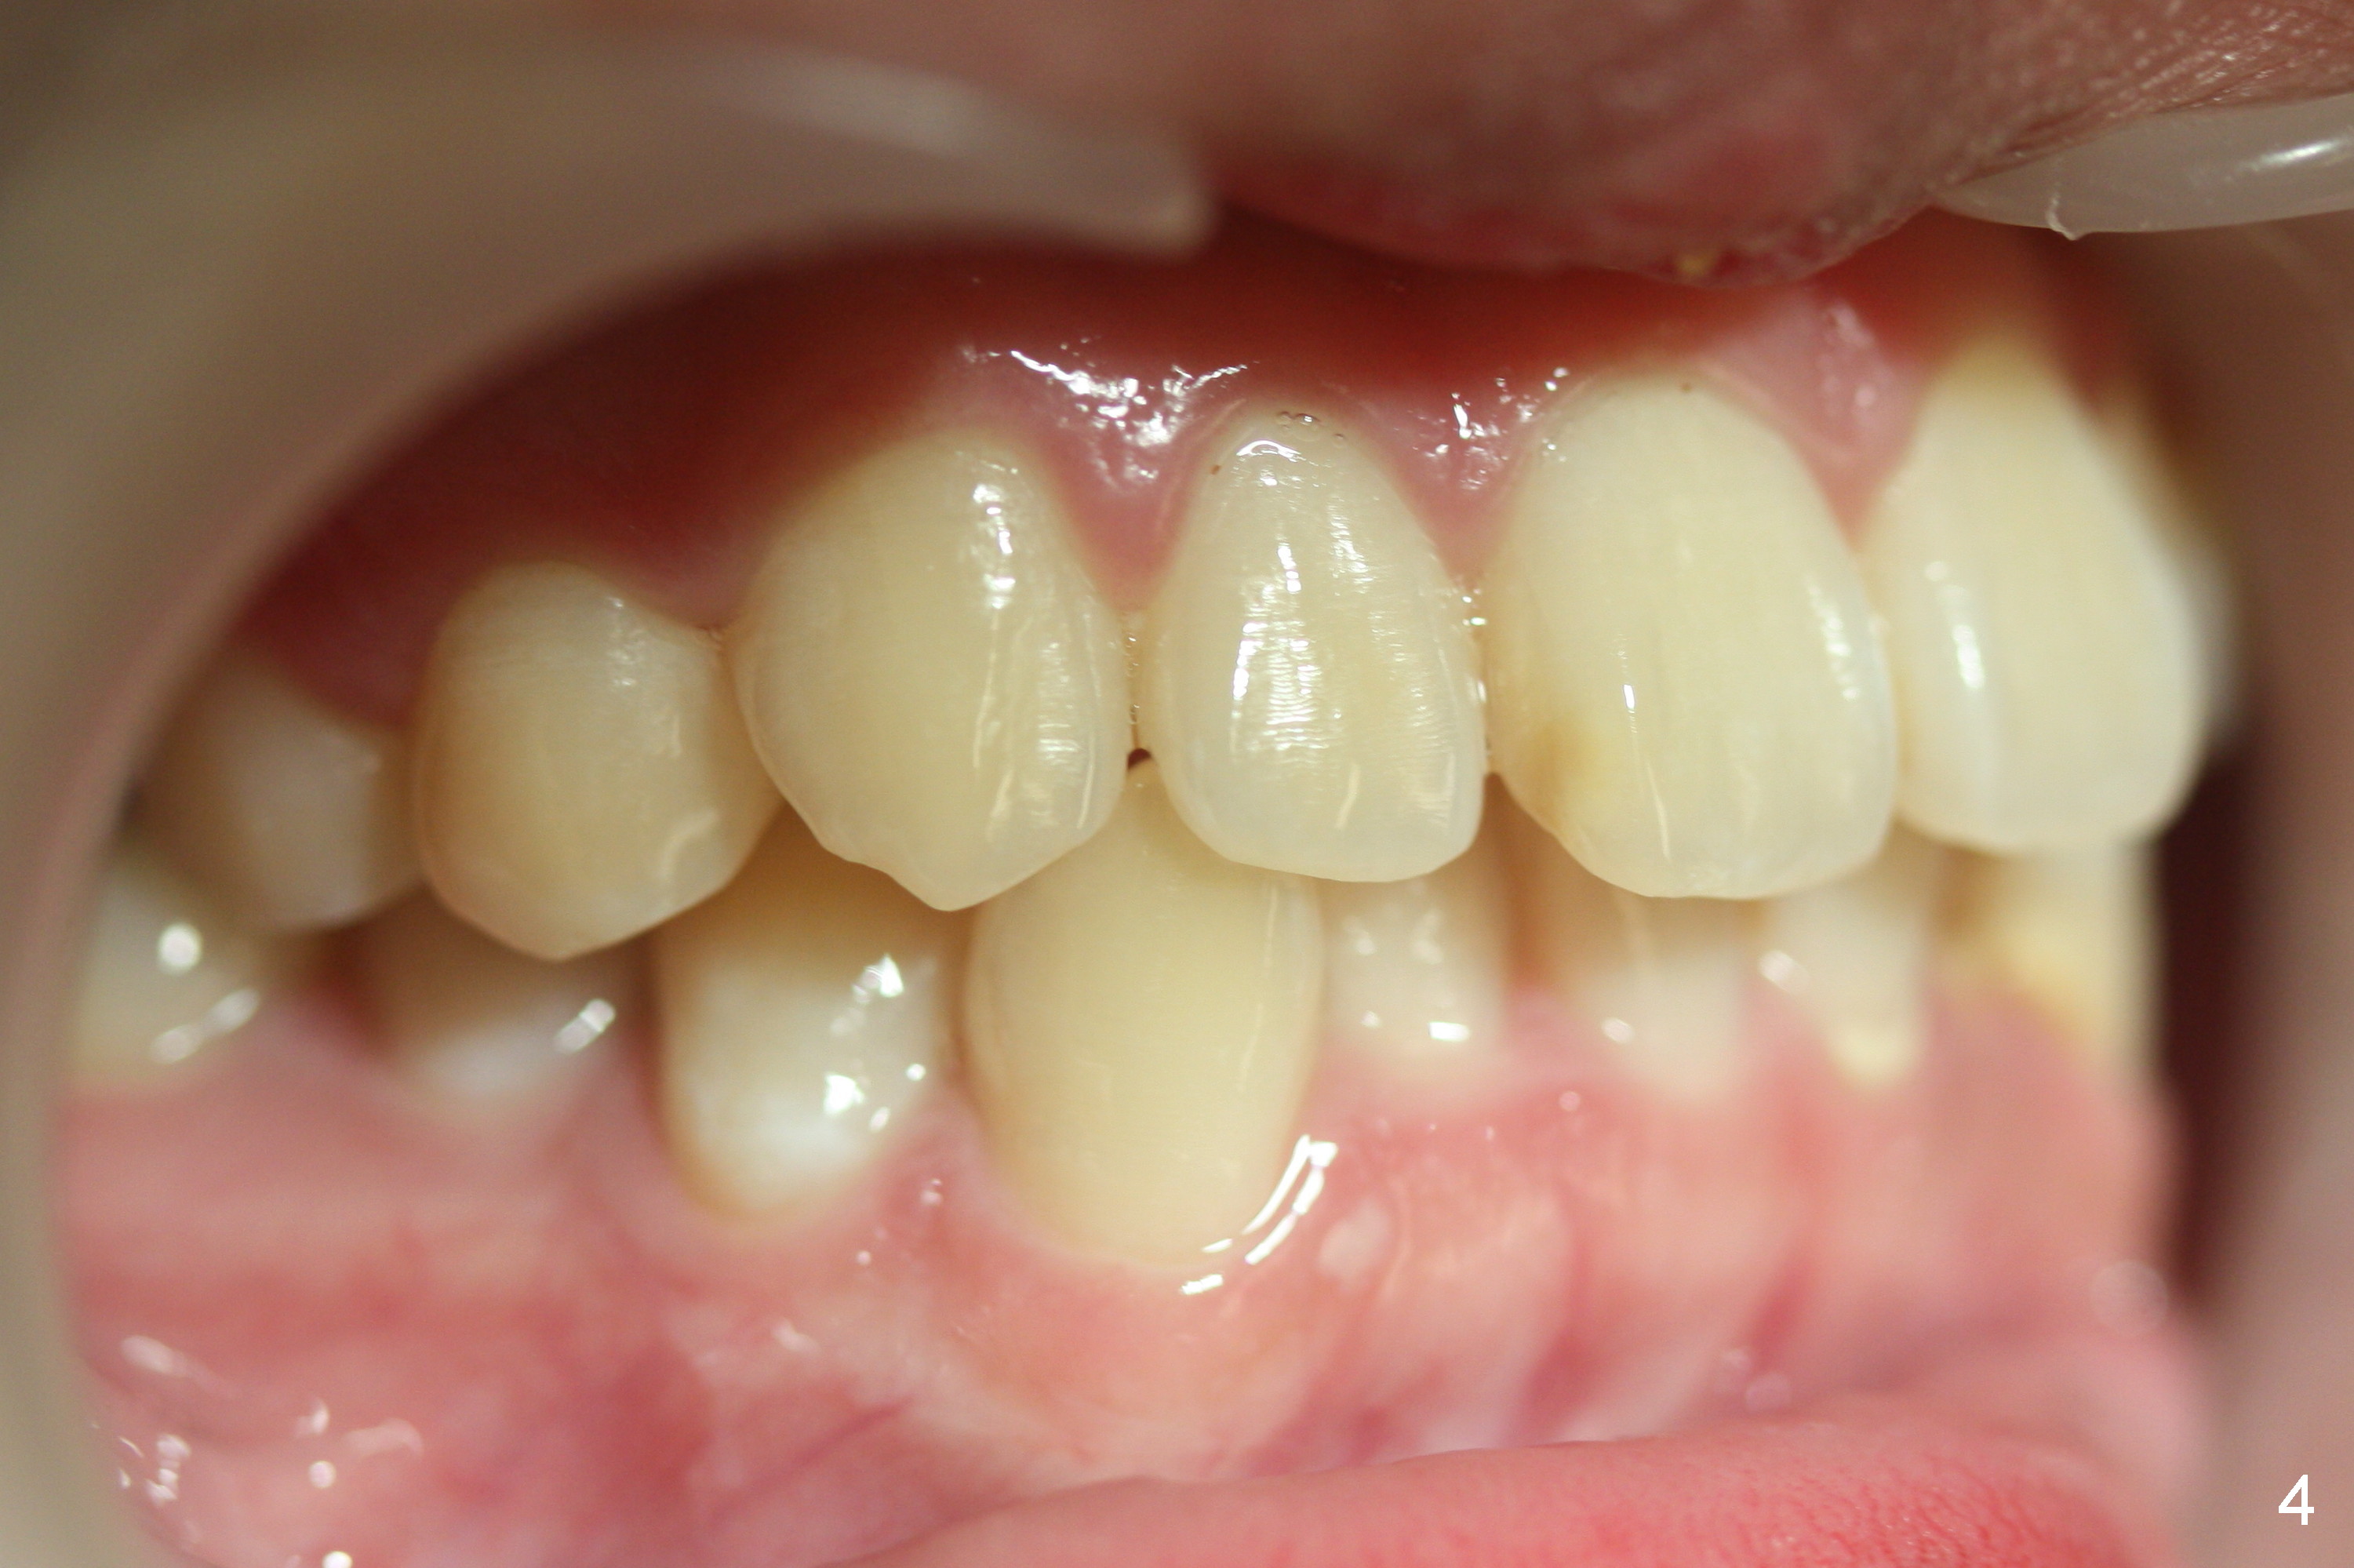

A 15-year-old man wants to improve the facial appearance.

Xin Wei, DDS, PhD, MS 1st edition 02/27/2017, last revision 09/09/2018